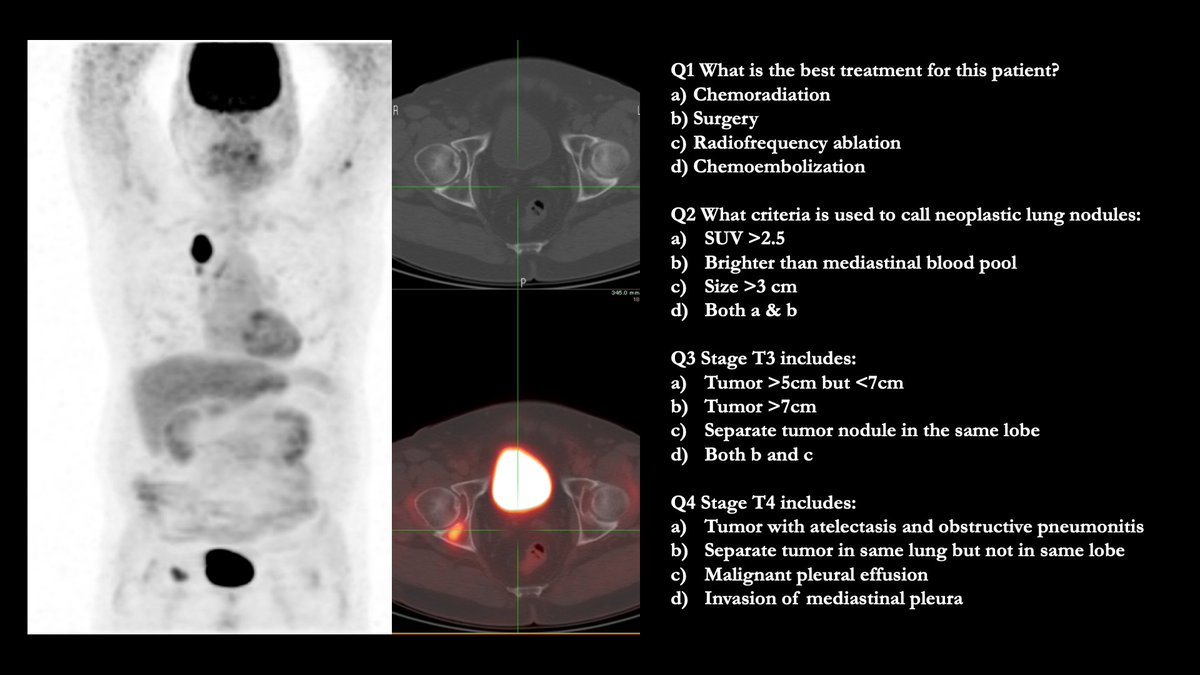

Case Challenge: # 57

Test your skills by providing answers in comments. Come back to check the answer key in 24 -48h.

Get all the cases at: nuclearmd.com/courses